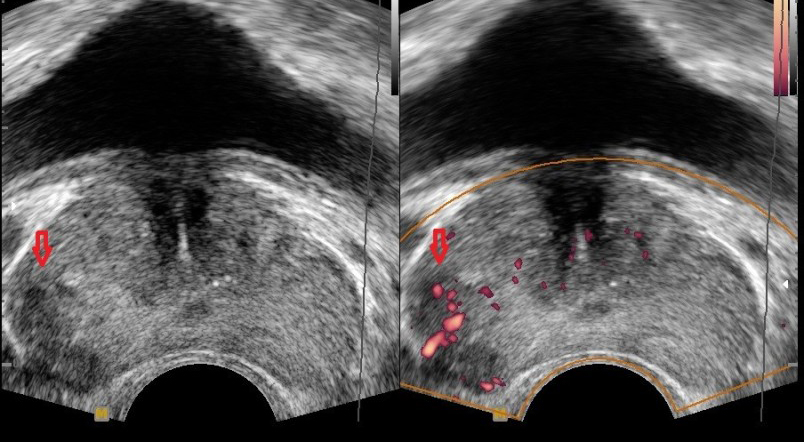

전립선암 체크를 통해 전립선암 psa수치를 검사할 수 있습니다. psa는 전립선특이 항원을 말해요. 주로 조기 진단에 사용됩니다. 혈중 psa 수치 증가는 전립선암을 진단하는 데 사용되기 그리해서 건강검진에서 psa 수치를 검사하다 보면 전립선암 진단을 할 수 있습니다.